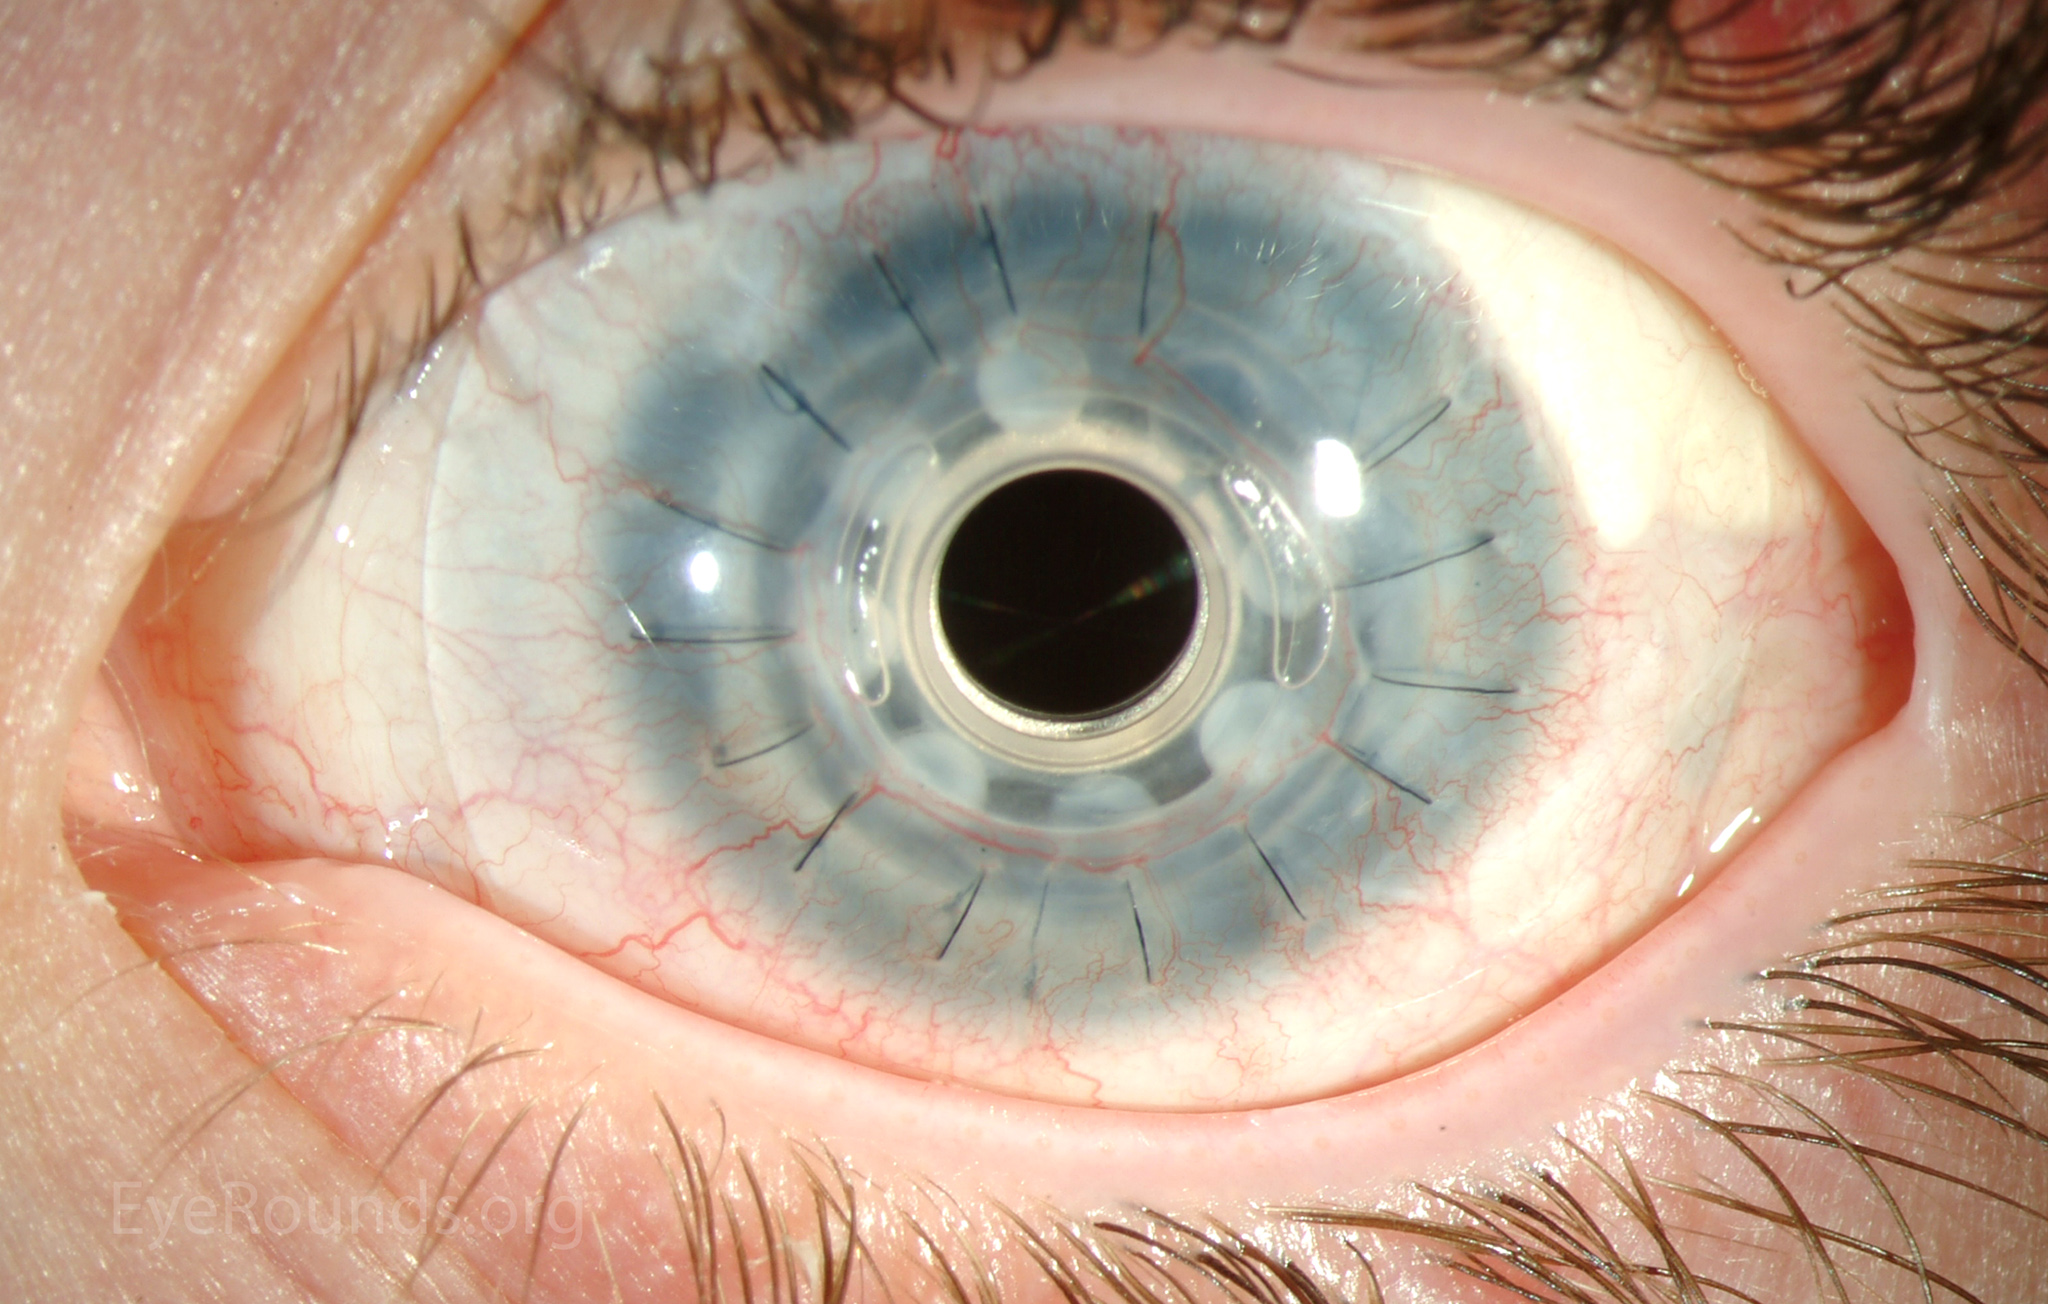

PK is a full-thickness transplant procedure, in which a trephine of an appropriate diameter is used to make a full-thickness resection of the patient's cornea, followed by placement of a full-thickness donor corneal graft. Interrupted and/or running sutures are placed in radial fashion at equal tension to minimize post-operative astigmatism (Figure 2). Later, the sutures are removed selectively to reduce the amount of astigmatism present. A transplant can last decades with proper care (Figure 3). While once the most prominent type of corneal transplant, PK has been supplanted by partial thickness techniques for endothelial dysfunction without significant stromal scarring. PKs are performed primarily for visually significant stromal scarring, opacities with an uncertain status of the endothelium or significant posterior corneal involvement, corneal ectasia (such as keratoconus and pellucid marginal degeneration, especially if there is history of hydrops), combined stromal and epithelial disease (such as Peters anomaly), and infectious or non-infectious corneal ulcerations or perforations (1, 14). A variant of the procedure, the mini-PK, can be used to treat more focal defects in the cornea (Figure 4).